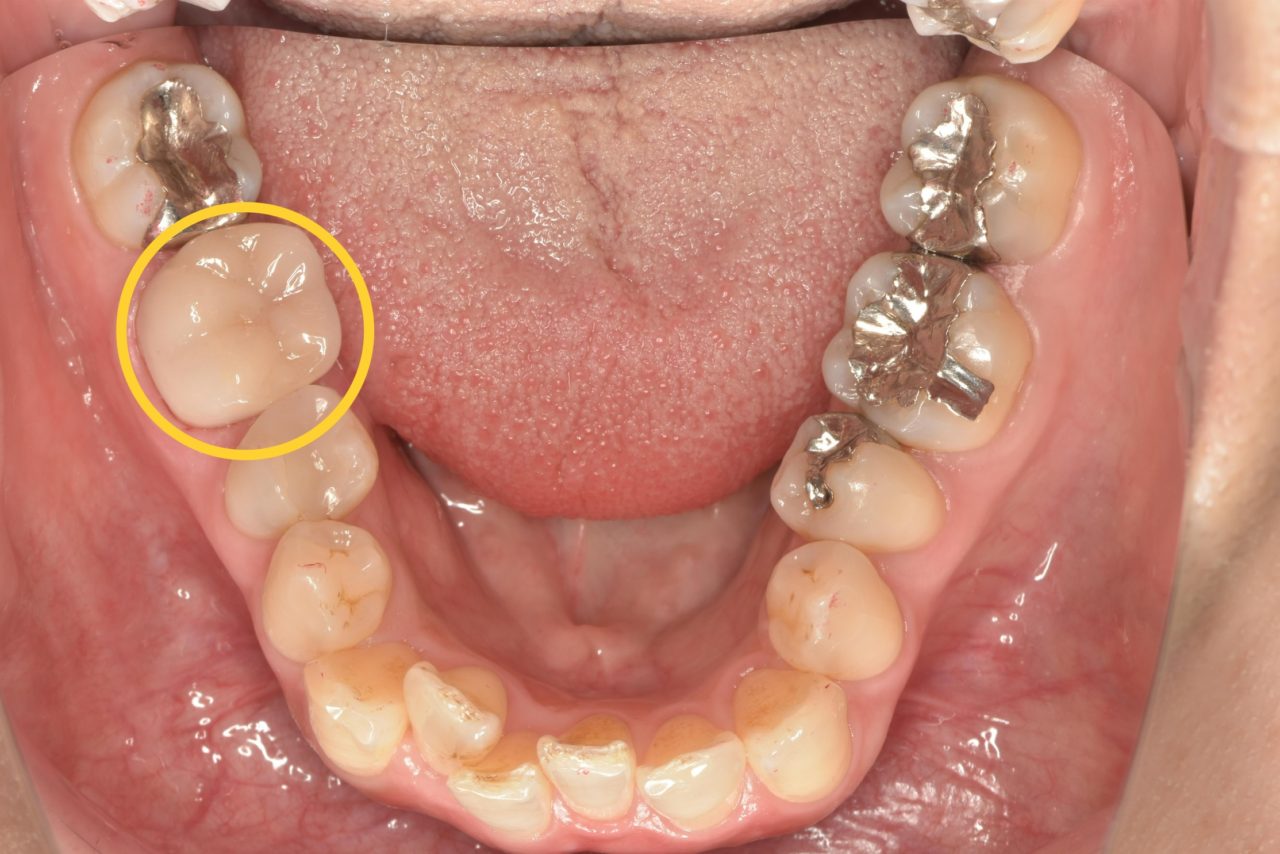

初診時の口腔内写真です。他院での根管治療の際にリーマーが折れ、歯の中に残ってしまっている症例です。

リーマーとは根管治療の時に使う器具のことです。

リーマーは治療中に折れてしまうことがあり、折れたことに気付かないまま、あるいは説明をせずに治療を終えてしまう歯科医院もあります。

その為、後から折れた器具が歯の中から見つかり、残念ながら患者様に説明がなされていないケースも見受けられます。 -

レントゲン写真をご覧ください。この直線的に写っている怪しい影が破折リーマーです。